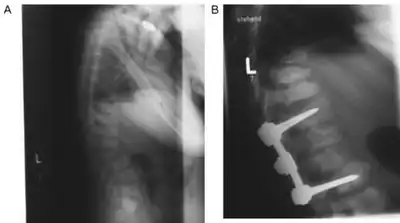

The first decade of life is characterised by the development of hearing impairment, psychomotor delay, recurrent infections, especially upper airway infections, pulmonary infections and acute/serous otitis media infections.[7] Significant changes in a number of facial features may occur, such as: protruding forehead; flattened nasal bridge; small nose; wide mouth; and widely spaced teeth.[2] Muscular weakness or spinal abnormalities can occur due to the build-up of storage materials in the muscle.[2]

There is no cure for congenital alpha-mannosidosis, and in general, the approach to management is proactive, with the aim of preventing emerging complications. After a full physical examination, physicians should focus on the known complications of alpha-mannosidosis, such as hydrocephalus, otitis media, hearing loss, dental caries, joint symptoms, kyphoscoliosis, and mental state.[2] Treatment is often limited to reducing or controlling the symptoms of the condition by, for example, medications to control seizures, hearing aids to ameliorate hearing loss, and routine physical therapy to assist with muscular pain and weakness.[2] In some cases, a wheelchair may be appropriate if muscle or spinal impairments immobilize the individual affected.